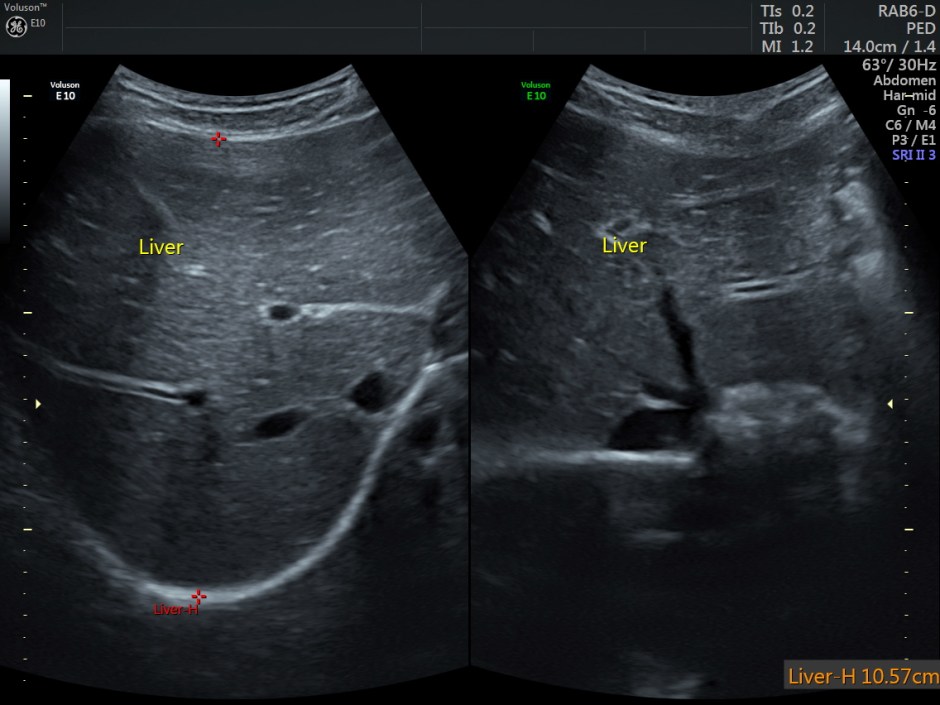

The scan revealed the following findings:

Normal appearing liver and portal venous system.

Other laboratory studies may be directed by history, physical examination, peripheral smear, and other laboratory findings. Ultrasonography is used to estimate the spleen size since the physical examination occasionally does not detect significant splenomegaly. Chest radiography, electrocardiography (ECG), and other studies are used to evaluate cardiopulmonary status.